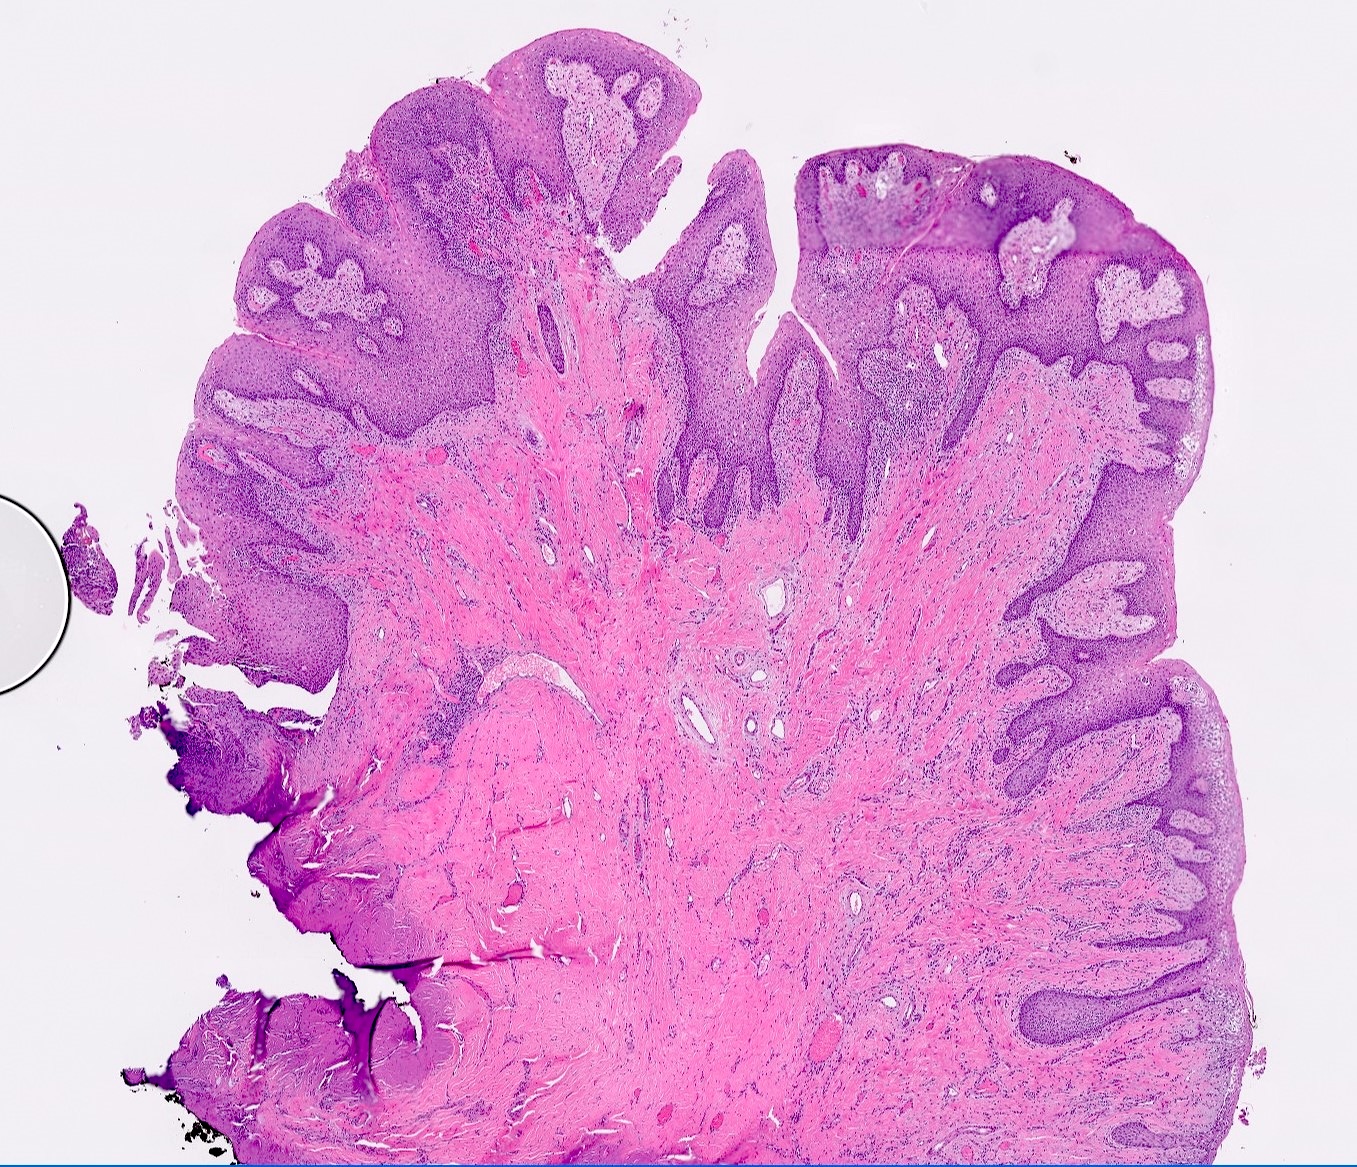

- Hyperplastic keratinized squamous mucosa overlying dense nodular connective tissue and variable inflammatory infiltrate (Acta Histochem 2016;118:451, Head Neck Pathol 2019;13:103)

- Underlying connective tissue is variably collagenized with scant bland spindled fibroblasts (Head Neck Pathol 2019;13:103)

- Pseudoepitheliomatous hyperplasia or secondary candidal colonization may be present

C. Inflammatory fibrous hyperplasia. The image shows squamous mucosa overlying a dense collagenous proliferation with focal chronic inflammation. Answer A is incorrect because amyloidosis is an accumulation of an acellular eosinophilic amorphous material in the submucosa. Answer B is incorrect because giant cell fibroma is not related to a history of chronic irritation. Morphologically the submucosa contains numerous stellate fibroblasts that can be multinucleated. Answer D is incorrect because solitary fibrous tumor is a cellular and vascular neoplastic proliferation; it does not have abundant reactive collagen.